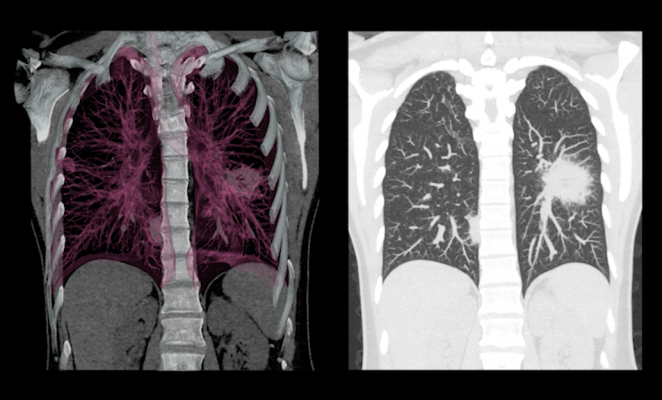

YKI Lampung tidak bergerak sendiri; mereka menggandeng PT Sinergi Global Alkesindo yang menghadirkan teknologi kecerdasan buatan (AI) untuk skrining paru-paru dengan akurasi tinggi. Di sisi lain, dukungan penuh datang dari RSUD Abdul Moeloek sebagai pusat rujukan utama di Lampung yang siap menindaklanjuti hasil deteksi dini dengan layanan onkologi yang lengkap. Hal ini dilakukan karena fakta lapangan menunjukkan banyak pasien baru mencari bantuan medis saat sel kanker sudah menyebar.